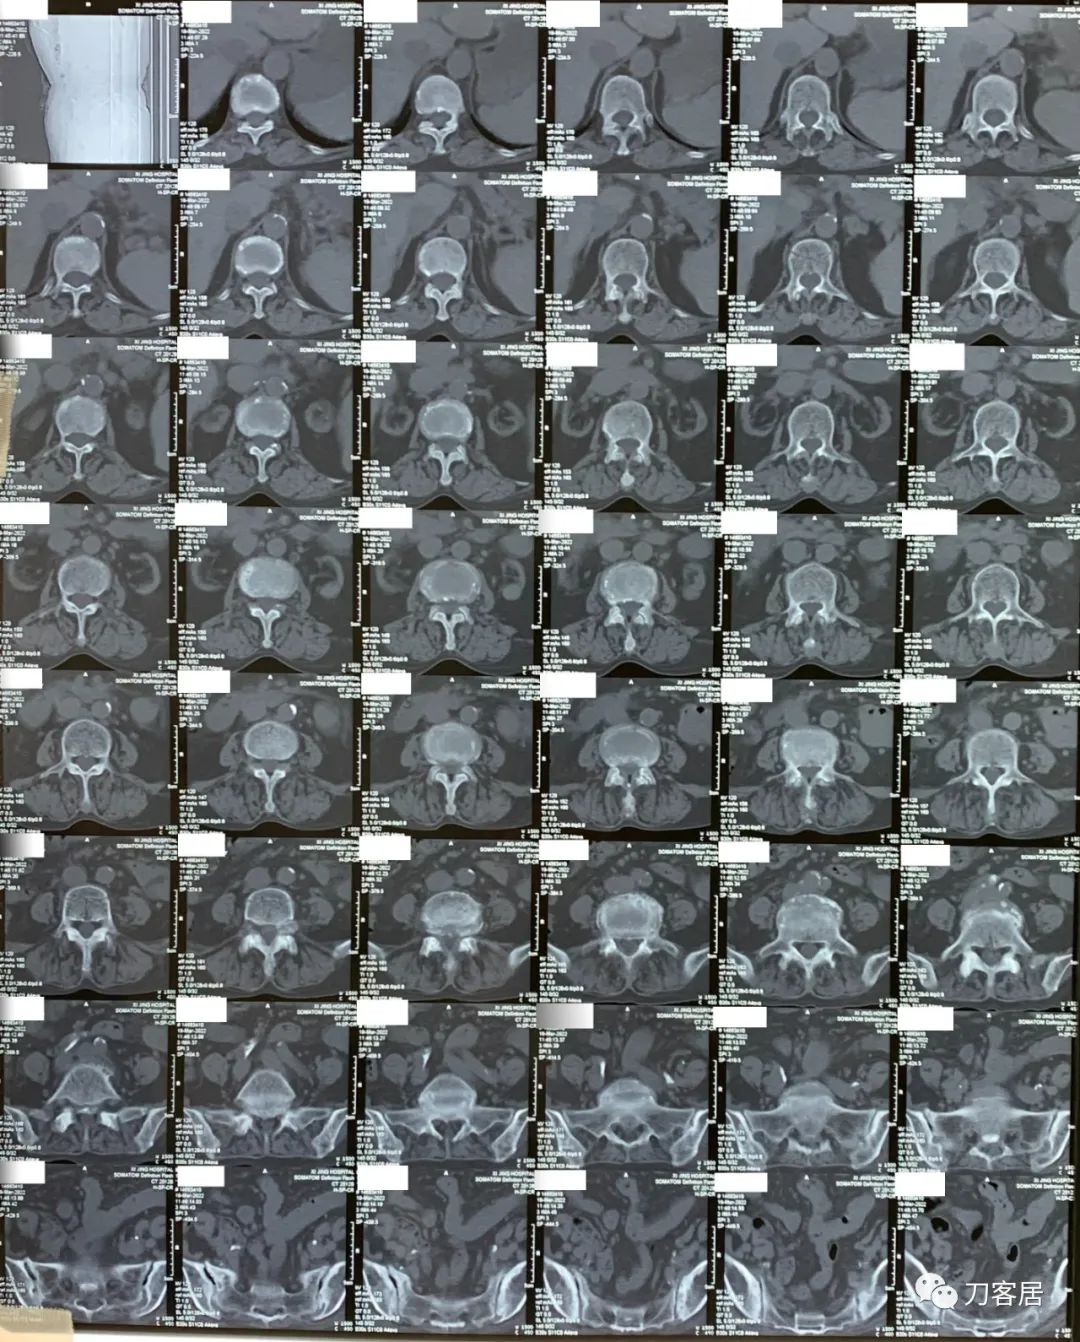

3月19日在我院神经外科门诊就诊时,做了腰椎CT平扫。腰椎CT提示腰4-5,腰5骶1椎间盘突出,腰4-骶1椎管狭窄。

图1. 20220319西京医院腰椎CT01

图2. 20220319西京医院腰椎CT02

图3. 20220319西京医院腰椎CT03

图4. 20220319西京医院腰椎CT04